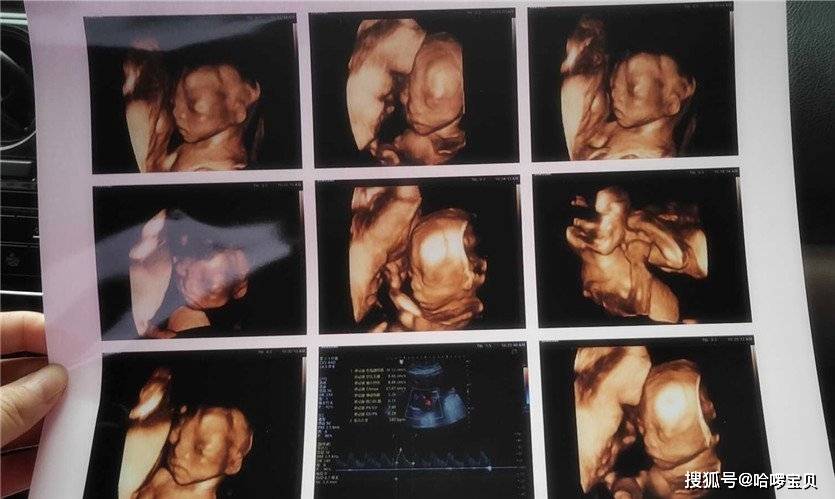

孕妈做四维被宝宝“丑”哭,这些四维彩超知识孕妈必知每个准妈妈,都希望自己的宝宝能生的漂漂亮亮的,在宝宝还没出生的时候,父母就开始猜想肚子里的宝宝会更像谁多一点。 然而孕妈到了做四维彩超的时候,是宝宝第一次拍照,这时候孕妈可以从彩超中大致看出宝宝的模样。 因此很多孕妈就会特别期待自己做四维彩超的时间,希望自己可...

准妈妈必知:四维彩超及生出漂亮宝宝的秘诀每位准妈妈都盼望着自己的宝宝能拥有可爱的模样。在宝宝尚未出世时,父母们便开始猜测腹中宝宝更像谁。 当孕妈进行四维彩超时,这相当于为宝宝拍了第一张照片,此时孕妈能从彩超中大致窥见宝宝的样子。 因此,不少孕妈格外期待做四维彩超的时刻,渴望尽早目睹宝宝的模样,还想留...

做四维彩超宝宝表现各异,医生暗示有趣,检查很重要孕期的每一项产检,对于胎儿和准妈妈来说,都有着重要的意义。在众多产检中,被大家熟知并且较为关注的一项,是四维彩超。 很多人希望通过四维彩超可以提前看到宝宝的样子,以及在妈妈肚子里的“动态”情况。当然,更重要的是为了通过此项检查来确定胎儿的健康情况。 不少准妈妈...

四维彩超:胎宝不耐烦捂耳,孕期噪声危害竟这么大!四维彩超下,胎宝宝动来动去,突然不耐烦地捂住耳朵,看似可爱,宝宝却很“受伤”。孕期噪声对宝宝的影响不容小觑! 胎宝宝听力从孕4周就开始发育,孕24周左右听力系统发育完成,26 - 28周听觉中枢系统发育健全。从听力发育开始就要保护其听力,长期噪声会破坏发育,听到外界声音后更...

孕妈为做四维趴大厅座椅调整胎儿体位,四维这样做,才能轻松过关前不久,广州一名孕妇前往医院进行四维彩超检查,此时宝宝已有六个月大。由于胎儿的体位不当,孕妇在检查过程中被医生要求调整体位多达四... 大排畸的检出率是多少? 这几乎是很多孕妇共同关心的问题,实际上每次检查的成功与否受到多种因素的共同影响,包括孕妇腹部脂肪的厚度、羊...